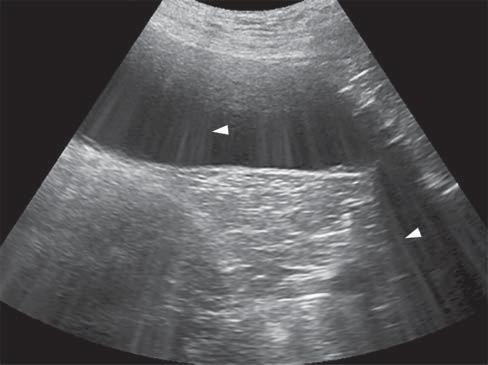

Edgeshadowing appearsasdiscrete,triangular zonesoflowamplitude,attheedgeofacurved structure(Figure1.14A).When,thecurvedstructure isfluidfilled,theedgeshadowingartifactbordersthe enhancementartifact.Thistypeofrefractiveshadowingcanbeconfusing,especiallywhenitoccursatthe

Figure1.14. Edgeshadowingandrefraction.A,B: Edgeshadowing(arrowheads)isoftenseeninprolongationoftherenal pole.LK,leftkidney. C: Thecurvatureofthebladderwallcausesbeamrefraction,whichresultsinanacousticshadow(arrowheads)inthisdogwithechogenicperitonealeffusion(*).Aholeinthebladderwall(arrow)isartifactuallycreated. D: Inanother dogwithcardiactamponadeandmarkedperitonealeffusion(*),theartifactualholeinthebladderwall(arrow)isattenuated byrepositioningthetransducerwithadifferentangulation.